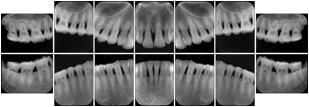

3. A dental provider wishes to capture a series of DICOM IO images for the patient’s dentition. The tooth morphology, teeth are divided into molars, premolars, canines and incisors, and a number of images for each jaw. The anatomic information was captured utilizing the triplet of schema. This standard code sequence is based on ISO 3950-2010, Dentistry - Designation system for teeth and areas of the oral cavity.

Every IO image should have anatomic information either through the primary or modifier sequence.

In most standard cases, images are oriented in structured layouts. These structured displays are useful to be shared between providers for reference purposes.

Table OO.1.1-1 shows structured display standard templates, where Viewset ID is based on the Japanese Society for Oral and Maxillofacial Radiology (JSOMR) classification provided by JIRA (Japan Medical Imaging and Radiological Systems Industries Association, www.jira-net.or.jp). Expected or typical teeth to be imaged location, region and designation codes are based on ISO 3950-2010, Dentistry - Designation system for teeth and areas of the oral cavity. For all the hanging protocols listed in OO.1.1-1, the value to use for Hanging Protocol Creator (0072,0008) is "JSOMR" and the value to use for Hanging Protocol Name (0072,0002) does not include "JSOMR" (e.g., "DL-S001A", not "JSOMR DL-S001A").